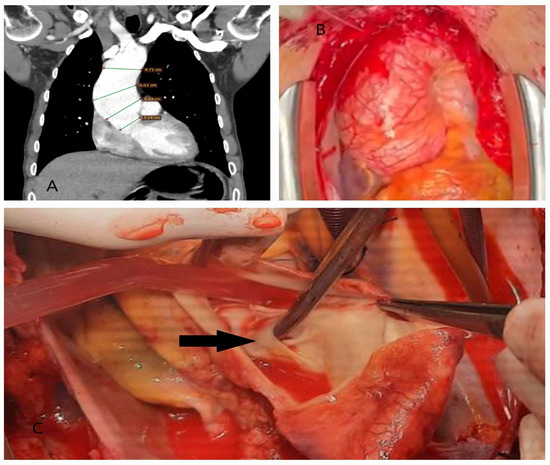

5.2.3. Computed Tomography